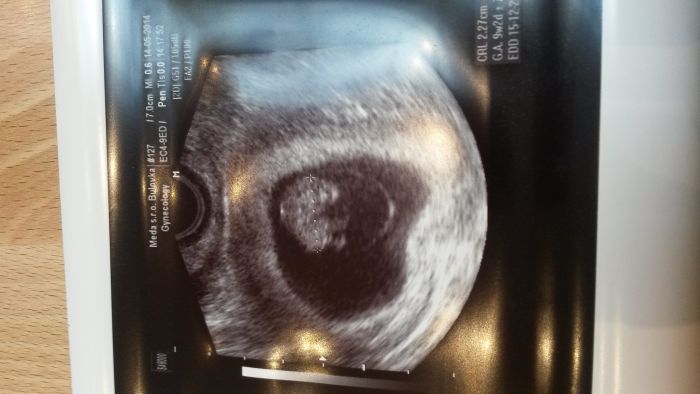

[540737] podle ms jsem byla vcera 9 +3 dneska teda 9+4

Pěkná fotka Karolino, já byla na kontrole minulý týden v 6+1 a mimi mělo 5,2 mm

Já byla v pondělí a měli jsme 2,70cm.Moje je to taky druhý a přítelovo první,jsem na něj zvědavá,hlavně u porodu

No vidiš Kati já byla taky 6+1 a měli jsme jen 2mm

Já byla 6+2 a měli jsme prý 3mm,dr.se divila,že už vidíme srdíčko,ale šlo vidět krásně :-)